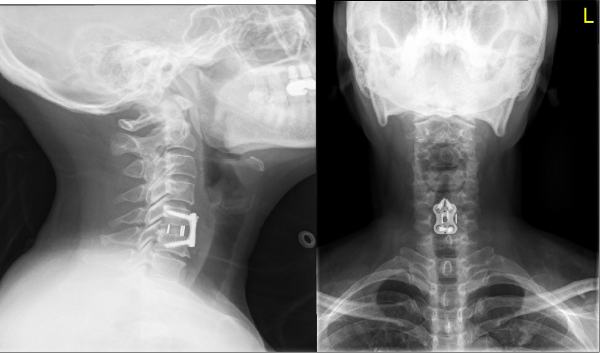

据悉,52岁的患者张女士因长期颈肩疼痛伴下肢无力、行走不稳,确诊为“颈椎间盘突出(C6-7节段)伴脊髓压迫”,既往因颈椎病行前路椎间融合(C5-6节段)后伴有颈椎活动受限,邻近节段退变加重进而出现症状。传统颈椎融合术虽能解除压迫,但会导致手术节段活动受限,且可能加速相邻节段退变。考虑到患者希望保留颈椎活动功能、尽快回归工作,李强主任牵头组织多学科讨论,最终确定采用“颈椎间盘置换术”这一先进术式。

术前正侧位X线